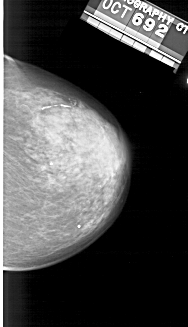

A_1393_1.RIGHT_CC

RIGHT_CC LINES 4576 PIXELS_PER_LINE 2626 BITS_PER_PIXEL 12 RESOLUTION 43.5 NON_OVERLAY